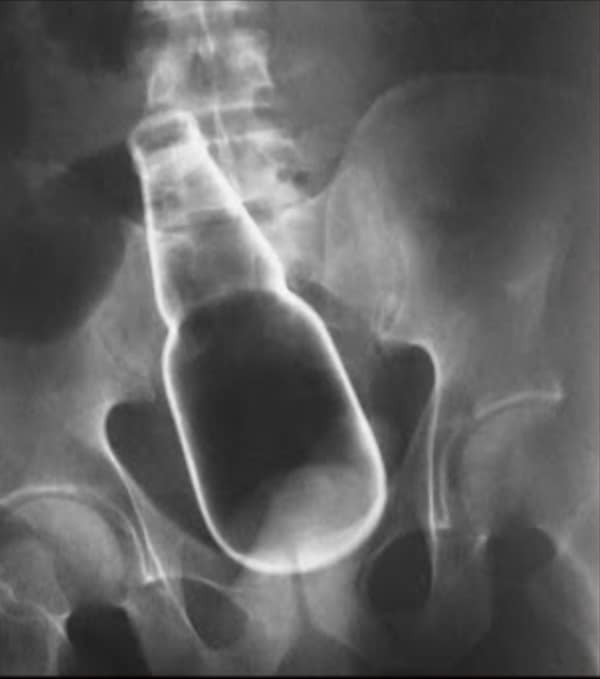

Weird xray photos

I used to think that nothing could surprise me anymore—until I stumbled upon some weird x-ray photos that made me reconsider my stance on human ingenuity (or lack thereof). Apparently, some people have a knack for getting objects lodged where they absolutely shouldn’t be. If you’ve ever wondered how not to use everyday items, these images might provide some unintended guidance.

This collection showcases 31 bizarre x-ray images that defy logic and anatomy textbooks alike. Each photo reveals unexpected objects making cameo appearances inside the human body, turning medical imaging into a gallery of the absurd. From common household items inexplicably found in unusual places to anomalies that would leave even seasoned doctors scratching their heads, these images offer a perplexing glimpse into the more “creative” side of medical emergencies. They highlight the intersection of curiosity, misadventure, and perhaps a dash of poor decision-making, all captured through the lens of radiology.